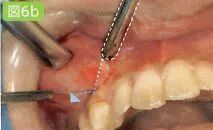

翻瓣分离

利用骨膜分离器将牙龈、粘膜、骨膜从牙骨上分离开来,暴露拔牙部位的牙槽骨。

吸唾器的目的

利用吸唾器清除分离器插入引起的出血,保证术野的清晰

观察骨膜分离器插入的部位。另外,将分离部位的出血吸引干净,以保证视野的清晰度。

刮匙怎么使用拔牙中吸唾器的使用技巧_https://www.jmylbn.com_新闻资讯_第19张